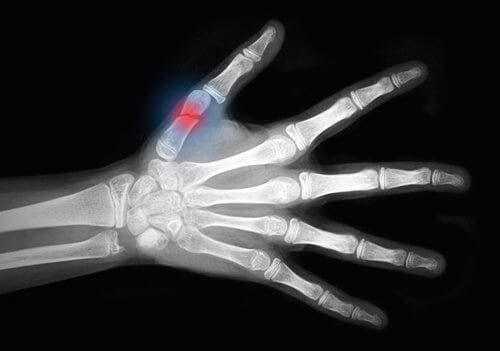

El cuerpo tiene la capacidad de regenerar el tejido óseo naturalmente, aunque a veces es un proceso lento. La curación de una fractura de hueso, tanto si es parcial como si es total, es un proceso complejo cuya velocidad y éxito dependerá de cada individuo.

De acuerdo con el contenido publicado en la plataforma Elsevier, el proceso de curación de las fracturas inicia de forma inmediata, por lo que a las dos semanas el hueso está unido por una red de fibrina. No obstante, la consolidación completa puede tomar hasta más de 6 meses en los casos más severos. Por fortuna, existen diversas técnicas que permiten acelerar este proceso.